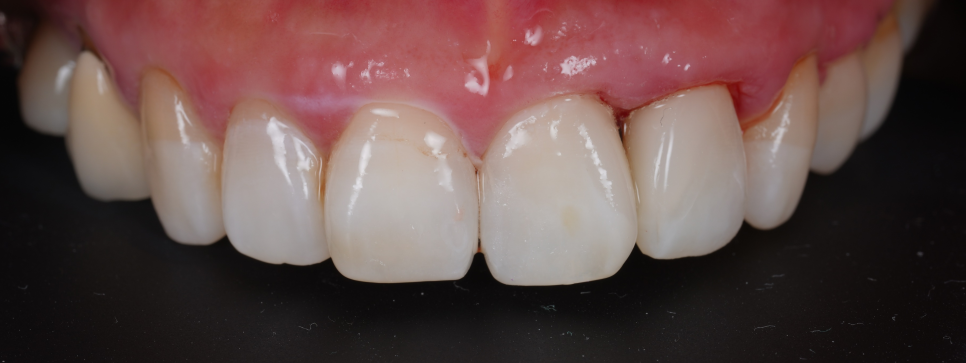

모든 과정을 마치고 환자분께서 "원장님, 이제야 정말 제 치아 같아요. 마음 놓고 크게 웃을 수 있겠어요!"라며 기뻐하시더라고요ㅎㅎ

촬영일 : 251230

저 또한 환자분이 겪으셨던 마음고생을 잘 알기에 큰 보람을 느꼈던 순간이었습니다.

주변 치아와 구분이 안 갈 정도로 자연스러운 투명감을 되찾았고 무엇보다 이제는 치실이 부드럽게 통과하며 잇몸을 깨끗하게 관리할 수 있게 되었죠^^